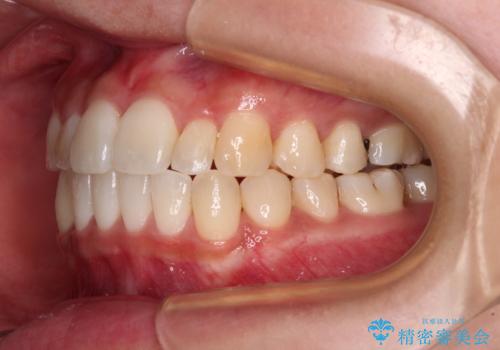

すきっ歯とオープンバイトをインビザラインで改善

- 前歯の上下スペースと前歯の隙間を気にして来院された患者様です。

インビザラインにより上下の前歯の隙間を閉じていくこととしました。

上下の隙間に舌が入り込むことが、すきっ歯やオープンバイトの原因であったため、舌の筋肉のトレーニングも並行して行い、後戻りの抑制を図りました。